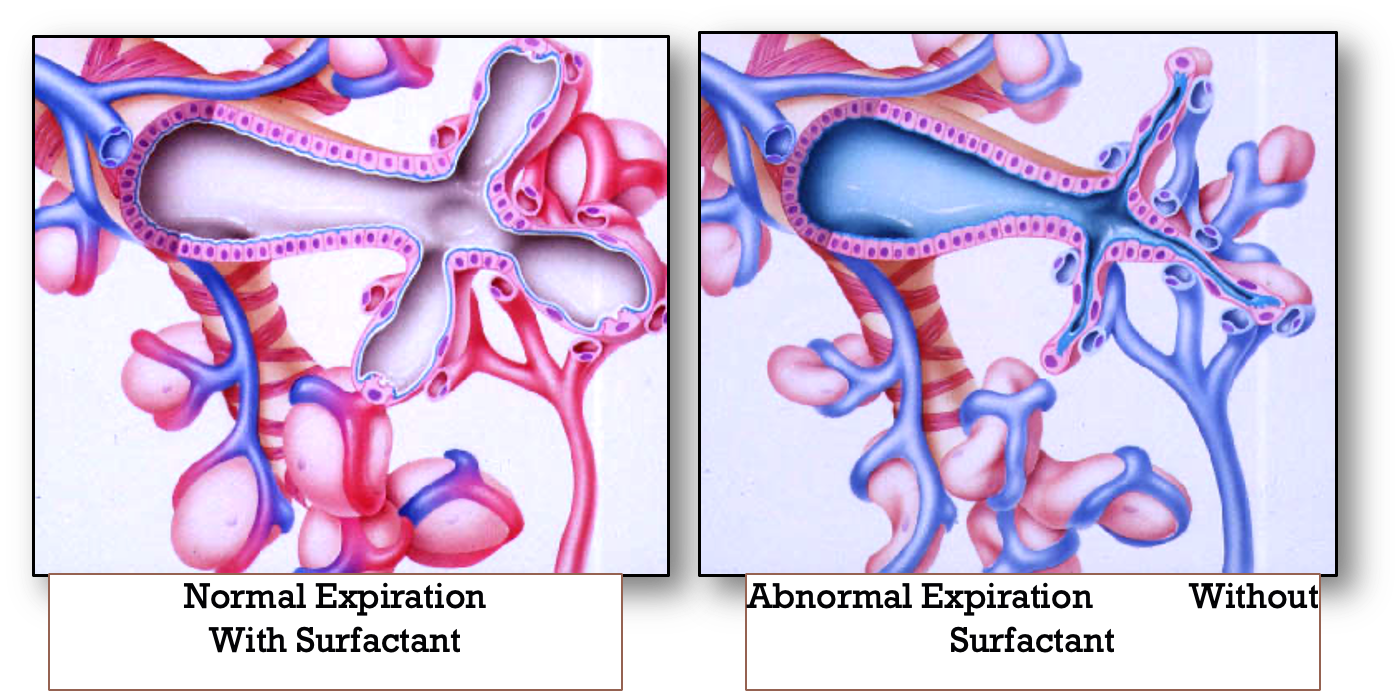

Respiratory distress syndrome develops in premature infants because of impaired surfactant synthesis and secretion leading to lung atelectasis. Surfactant is a mixture of lipids and proteins produced by type II pneumocytes in the lung epithelium. The absence of surfactant in the alveoli causes an increase in surface tension with consequent atelectasis at the end of expiration.

If not treated, such atelectasis leads to increased work of breathing, intrapulmonary shunting, ventilation-perfusion mismatch, hypoxia, and eventual respiratory failure. Subsequently, serum proteins that inhibit surfactant function leak into the alveoli and with other components form the hyaline membrane.